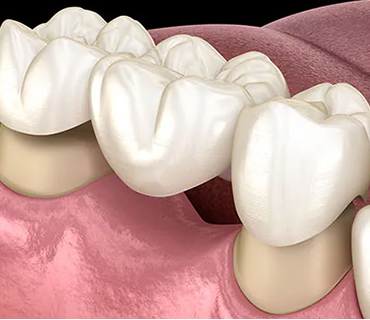

Bridges & Crowns

Dental crowns are used as caps on missing or fractured tooth

- It replaces large filling

- Restore teeth due to trauma

- Caps placed on RCT done tooth

- Discolored, misshaped tooth are replaced with the crown